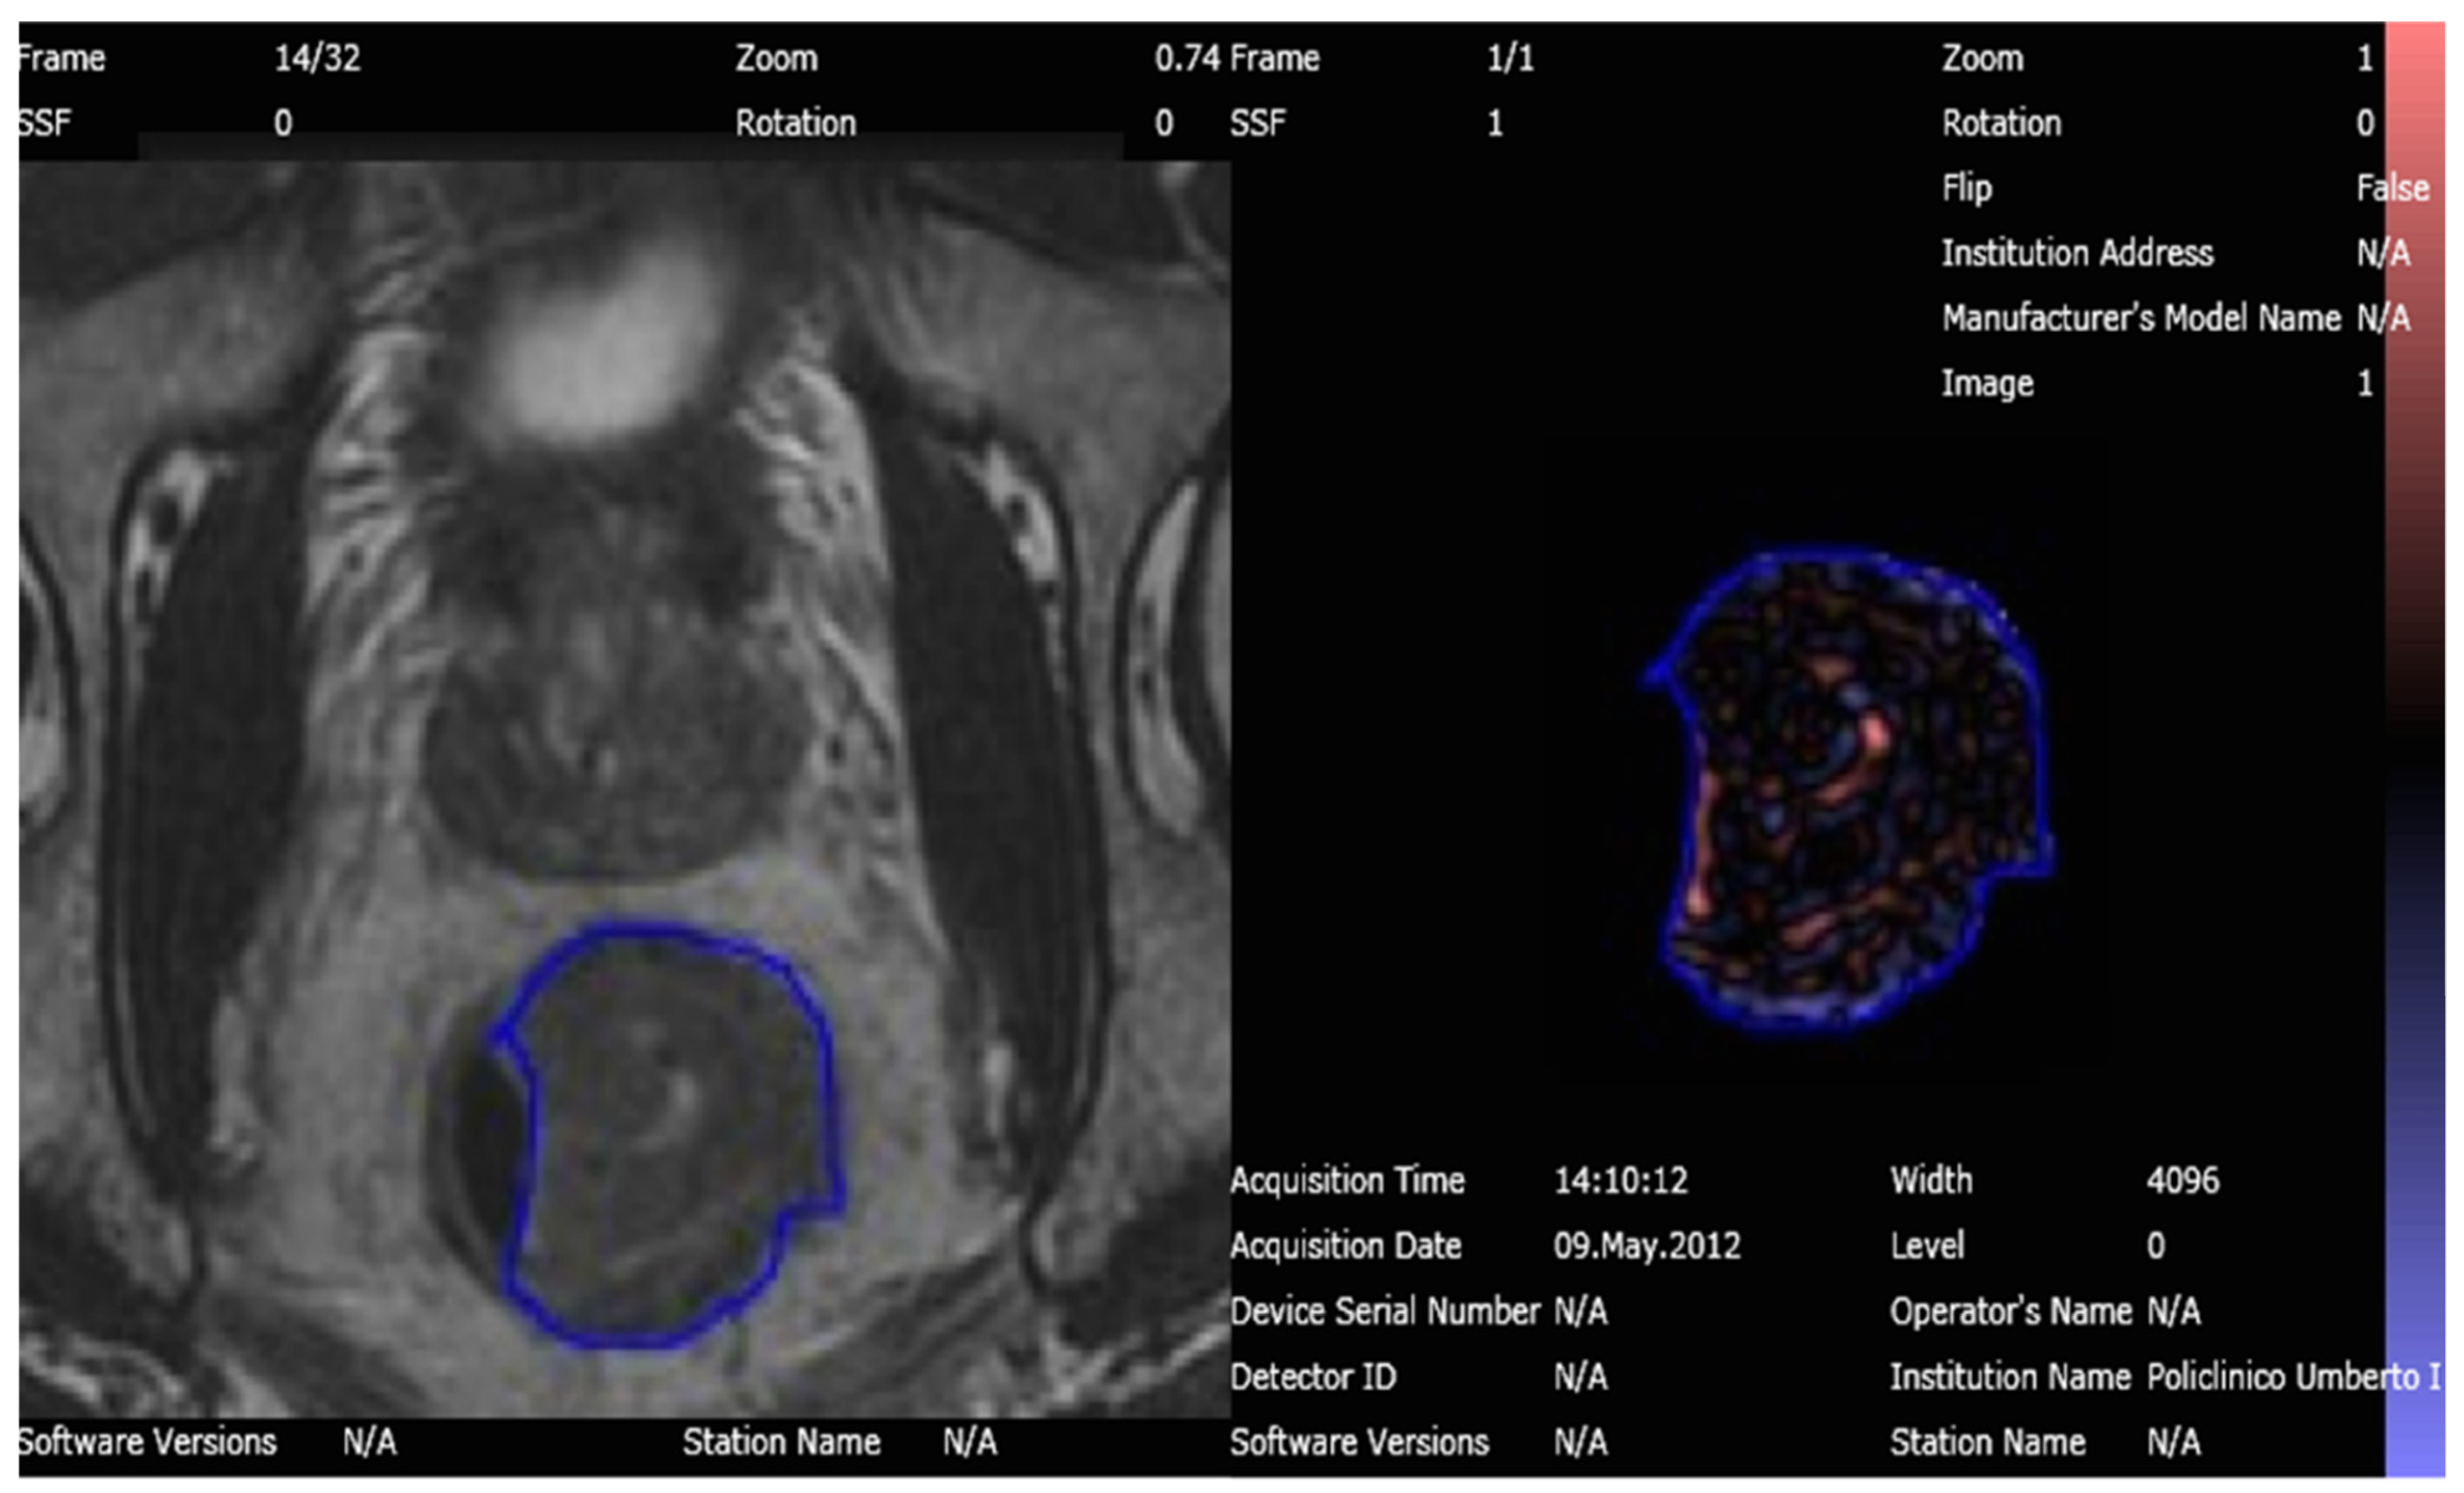

2.6. Texture Analysis

2.7. Artificial Intelligence Analysis